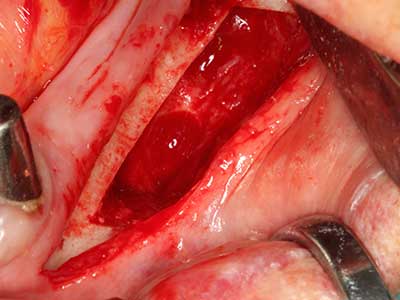

Indication: Preparation near nerves

Indication: Apical resection

When surgical procedures are performed on bone in the immediate vicinity of sensitive structures such as blood vessels or nerves, rotary instruments pose a significant risk of iatrogenic injury. Piezoelectric devices can be helpful for preparation of bone covers and removal of hard tissue close to nerves, particularly for exposure of nerves after iatrogenic injury but also during nerve lateralization for resective and reconstructive procedures or implant placement (Fig. 17-20). Light contact between the piezotip and the nerve does not generally result in damage but proceeding incautiously with saw-like motions or attachments where a residual bone substrate remains may cause temporary or even permanent nerve damage. However, the risk of damage is considered to be substantially lower than when using saws or milling instruments (Pereira, Gealh et al. 2014).